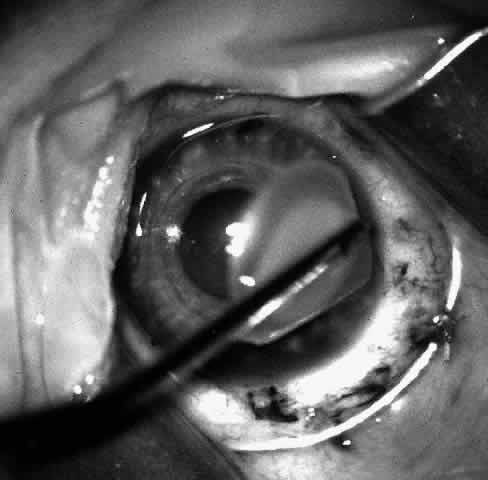

At this point, if intraocular surgery, that is, cataract extraction, pupilloplasty, or membranectomy, is to be done, it is performed through a limbal incision with a vitreous cutting instrument such as the Microvit or Ocutome (Fig. 8). The limbal incision may be closed with 8-0 polyglactin 910 (Vicryl) sutures. After the intraocular procedure is completed and before the epikeratophakia procedure is resumed, it is important to return the eye to normal pressure by injecting balanced salt solution. I prefer to accomplish this with a 30-gauge sharp paracentesis injection through clear cornea.

Fig. 8. After trephination, intraocular surgery may be carried out through a limbal approach if required. Note that the Flieringa ring shown is no longer routinely used.